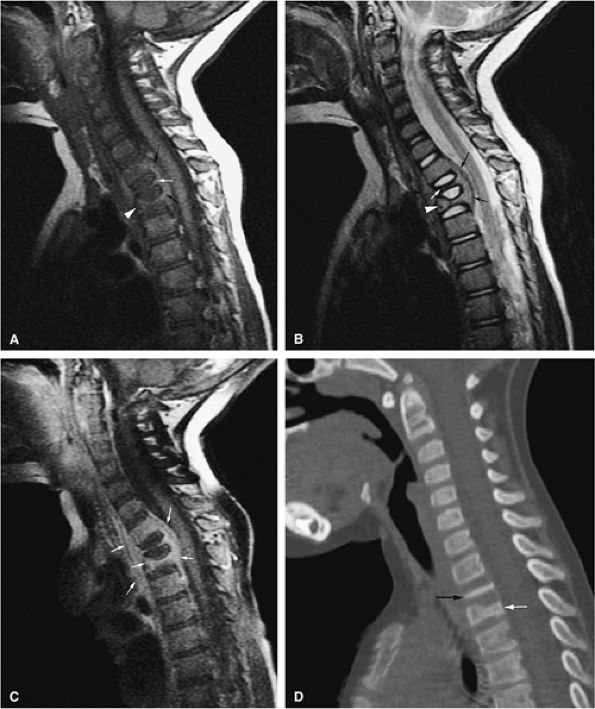

FIGURE 13.41 ● (A) Sagittal T1-weighted image shows complete collapse of the T2 vertebral body (white arrow) and greater than 50% collapse of the T3 vertebral body (white arrowhead). A surrounding soft-tissue mass is noted (black arrow). (B) Corresponding T2-weighted image shows collapse of the T2 (white arrow) and T3 (white arrowhead) vertebral bodies. A surrounding soft-tissue component is present (black arrows). (C) On a sagittal fat-suppressed T1-weighted image following the intravenous administration of gadolinium, there is diffuse enhancement of the tumor and soft-tissue component (arrows). (D) Sagittal CT image shows complete collapse of the T2 vertebral body (black arrow). Vertebral body height loss of T3 is also noted (white arrow).

|